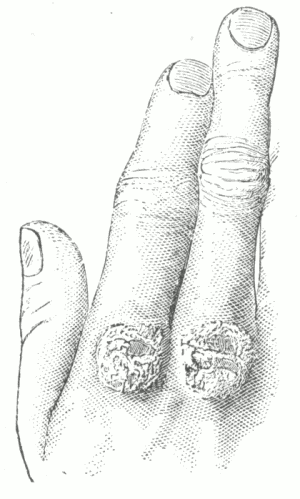

Fig. 11.

Erythema Multiforme, in which many of the lesions have become bullous—

Erythema Bullosum.

Does the eruption of erythema multiforme ever assume a vesicular or bullous character?

Yes. In exceptional instances, the inflammatory process may be sufficiently intense to produce vesiculation, usually at the summits of the papules—erythema vesiculosum; and in some instances, blebs may be formed—erythema bullosum. A vesicular or bullous lesion may become immediately surrounded by a ring-like vesicle or bleb, and outside of this another form; a patch may be made up of as many as several such rings—herpes iris. In the vesicular and bullous cases the lips and the mucous membranes of the mouth and nose also may be the seat of similar lesions.